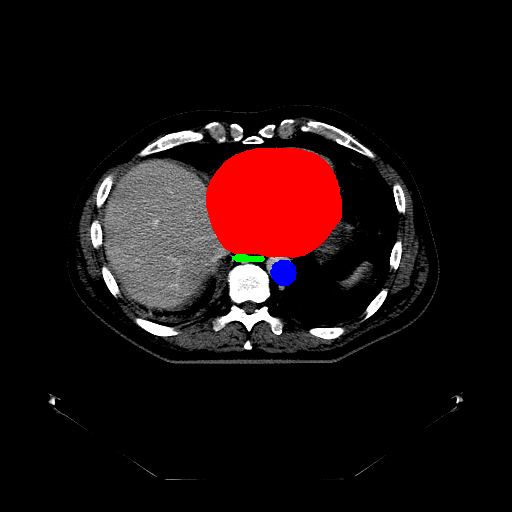

Case Study 3: Multi-Organ Segmentation

The cognition of artificial intelligence is important for computer-aided diagnostic. Multi-organ segmentation can help the machine understand the structure of the human body, which is very important for all the relevant tasks. Therefore, some research has focused on single- or multi-organ segmentation tasks, such as the liver([79, 80]) and the pancreas([81, 82]). In this case study, we use a VNet-based neural network to solve the multi-organ segmentation challenge, SegTHOR, [83]. The SegTHOR challenge includes about 40 CT images of the chest, and aims at the segmentation tasks of the heart, aorta, trachea, esophagus, and further more.

VI-1 Workflow and Implementation

As Fig. 11 shows, The workflow of this case study includes six parts: “input”, “pre-processing”, “dataset management”, “neural network”, “visualization”, and “analysis”. The “input” includes images of the chest and annotations.

“Pre-processing” rescales the range of the image values with a window width and a window level. Then, the input images are re-sampled with the “resample” tool to change their size. The “dataset management” function subsequently splits the dataset into a training and a testing set randomly, yet reproducibly.

“Neural network” employs VNet to train and validate the model, which can be used to segment organs from the chest. Then, the segmented images can be visualized via the “organ visualization” option, and the results can be analyzed with the “result analysis” tool to generate an MS-Excel based report.

VI-3 Result and Visualization